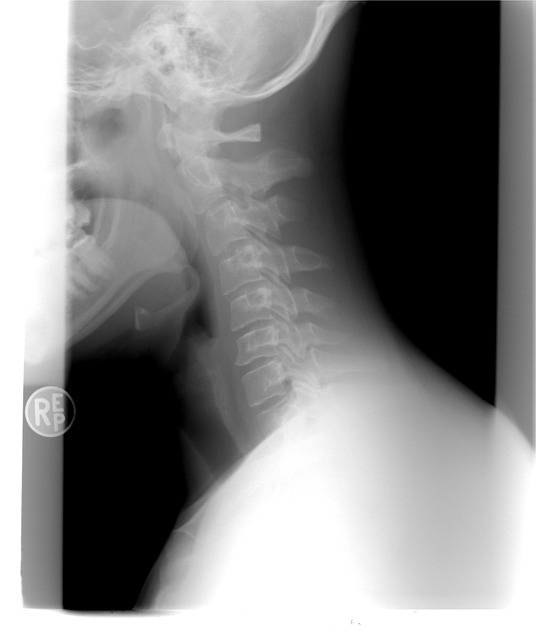

갑상선은 목에 위치하여 신진대사에 필요한 호르몬을 분비하는 내분비기관을 말하는데, 이 호르몬은 각종 대사에 필요하기 때문에 매우 중요한데요. 이런 갑상선 목부음 증상 등 이상 증세를 느끼는 이유는 세포성장이 과하게 이루어지는 등의 이유로 갑상선에 종양이 생겨서 이물감이 느껴지는 경우가 대부분입니다.